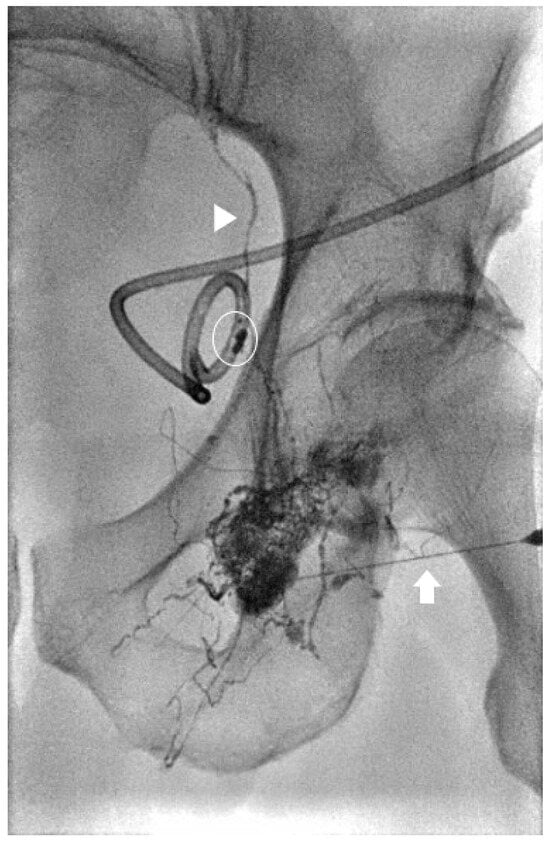

Figure 1. Spot image from an intra-nodal lymphangiogram for a 39-year-old patient with traumatic chylous ascites after retroperitoneal lymph node dissection. Lipiodol is seen filling the retroperitoneal lymphatics (arrowhead) and leaking into the peritoneal space (arrows).

Figure 2. Spot image the same patient in Figure 1 with a 22-gauge needle placed under fluoroscopy into the site of the lymphatic leak (arrow) prior to embolization.